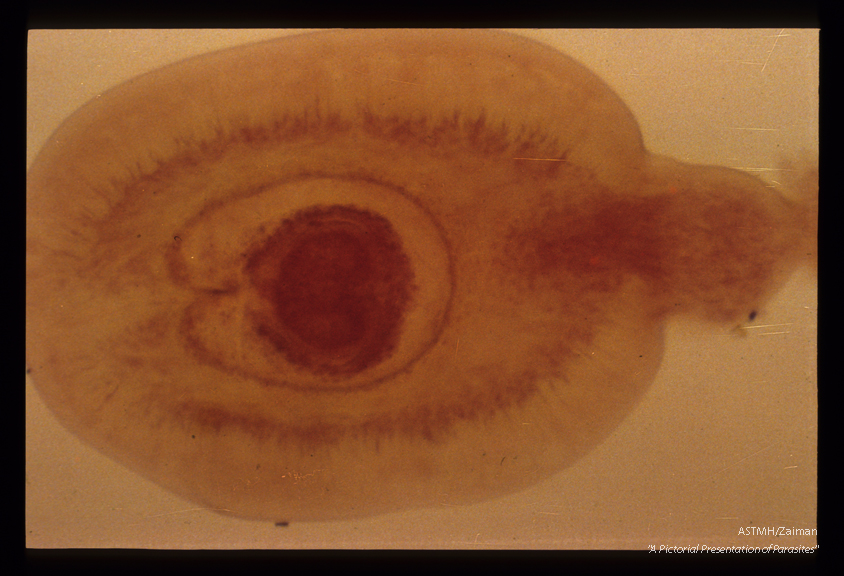

Cysticercoid larvae, from an insect intermediate host.

Hymenolepis diminuta

Description: Cysticercoid larvae, from an insect intermediate host.